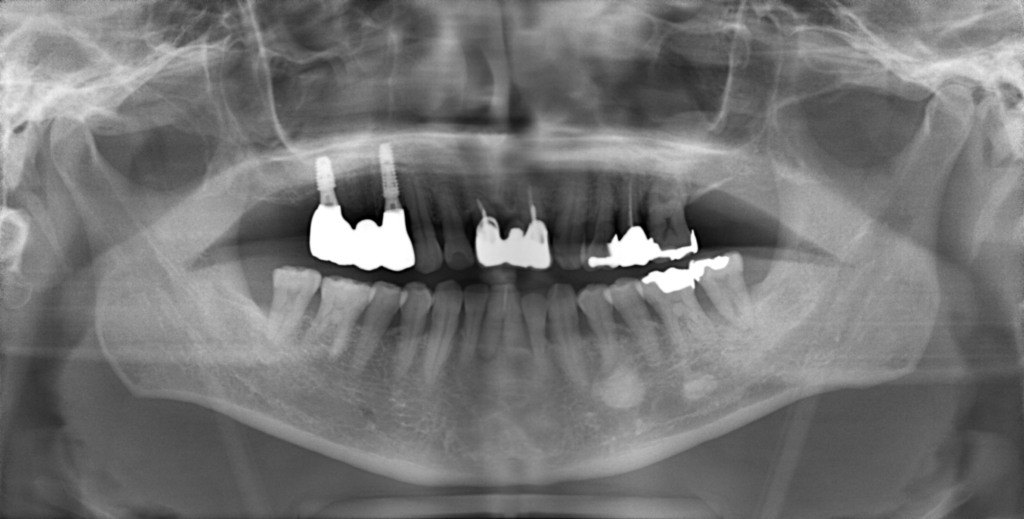

Y様インプラント実例 #44

左の上下の奥歯をインプラントで治療しています。

左下の奥歯は歯を抜くのと同時にインプラントの埋め込みを行っています。

被せものは上下、セラミックスで作っています。

治療前

治療後